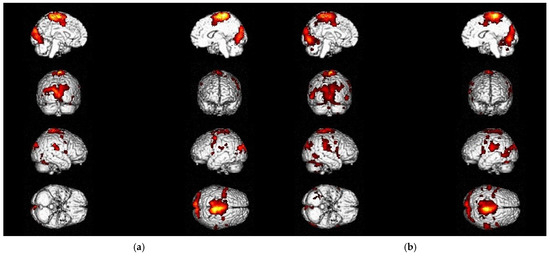

3.1. Utility of Chosen fMRI Paradigms in Acute Stroke Patients with Ataxic Symptoms

3.2. Changes in Activation Patterns During Recovery and Rehabilitation